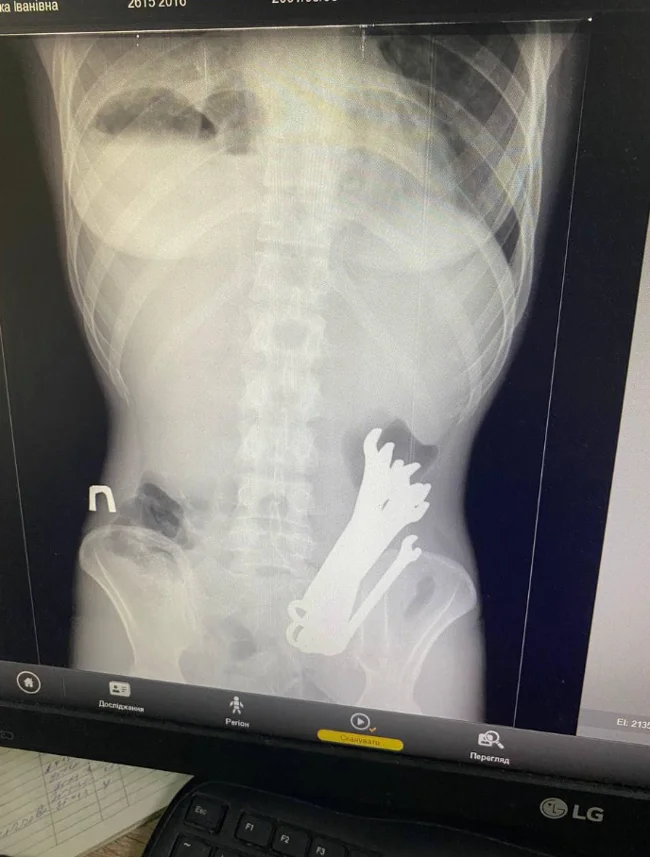

Украинец на спор проглотил шесть гаечных ключей (3 фото)

Покидать тело украинца ключи не спешили, и бедолагу пришлось оперировать. Об инциденте, который произошёл еще в августе, сообщили в отделении торакальной хирургии Черкасской областной больницы.

Мужчину госпитализировали с флегмоной шеи, разрывом пищевода на уровне глотки и средней трети, тотальным медиастинитом, эмпием плевры с правой стороны и опущением желудка.

Ключи в ходе операции успешно достали. Сам пациент через три недели был отпущен домой.